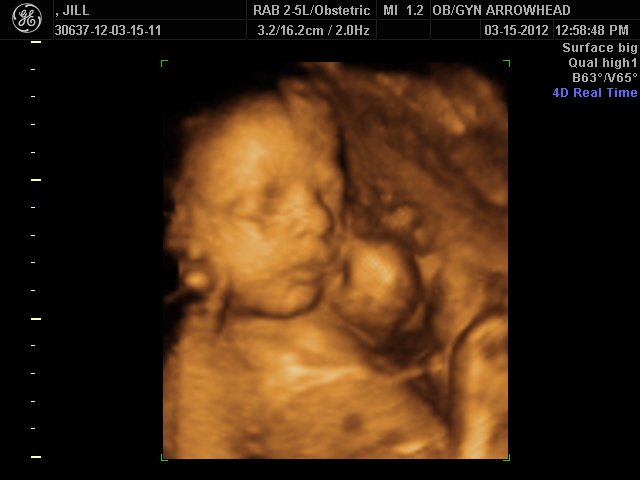

We offer complimentary 3D/4D Ultrasounds to all our OB patients around 30 weeks! The following photos are some examples of our work, shown with permission from our patients.